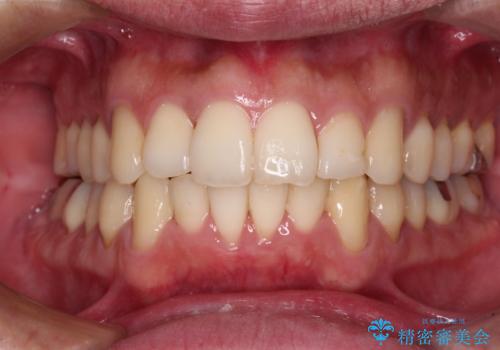

むし歯と前歯のデコボコを治したい インビザラインを使用した総合歯科治療

- 目立つ銀歯やむし歯、前歯のデコボコを気にして来院された患者様です。

デコボコはある程度改善できれば良いとのことでしたので、インビザラインの廉価版を用いて矯正治療を行うこととしました。

しっかりと装着時間を守ってくださり、来院のタイミングに合わせてインビザラインの装着期間を調整するなど、協力いただいたおかけで、1年半の期間で全てを終えることができました。